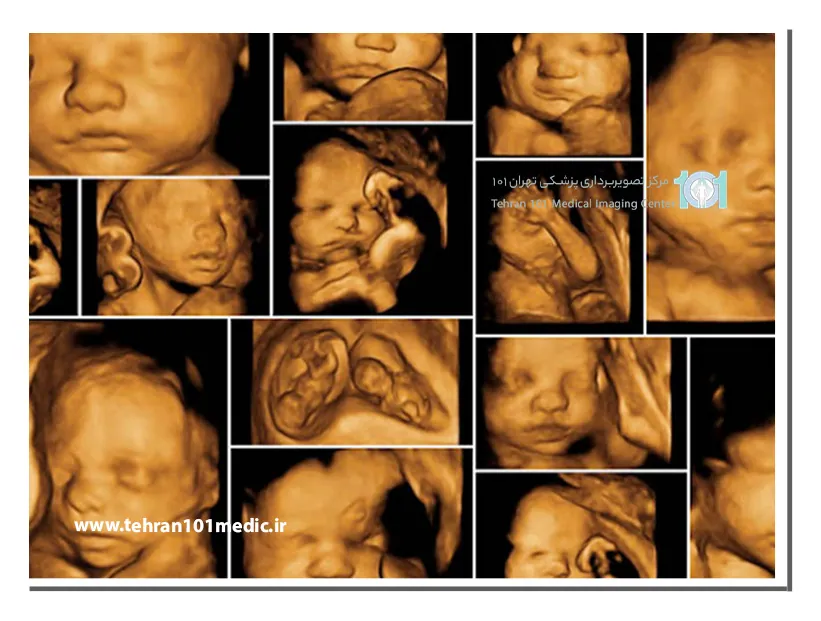

سونوگرافی آنومالی، که به آن سونوگرافی اواسط بارداری یا سونوگرافی تفصیلی نیز گفته میشود، یکی از انواع سونوگرافی است که در هفتههای ۱۸ تا ۲۲ بارداری انجام میشود. هدف از این سونوگرافی، بررسی دقیق اندامهای جنین و تشخیص هرگونه ناهنجاری یا نقص مادرزادی احتمالی است.

سونوگرافی آنومالی یک آزمایش مهم و ایمن است که با استفاده از امواج صوتی می تواند به والدین کمک کند تا در مورد سلامتی نوزاد خود آگاهی کامل داشته باشند. این سونوگرافی همچنین می تواند به پزشکان کمک کند تا در صورت وجود ناهنجاری ساختاری، مراقبت های لازم را برای نوزاد برنامه ریزی کنند.

در سونوگرافی آنومالی، متخصص سونوگرافی از یک پروب مخصوص برای ارسال امواج صوتی به داخل رحم استفاده میکند. این امواج صوتی پس از برخورد به اندامهای جنین، بازتاب میشوند و توسط پروب دریافت میشوند. سپس، این امواج صوتی بازتابشده توسط یک کامپیوتر به تصاویر تبدیل میشوند.

در طول سونوگرافی آنومالی، پزشک به دقت اندازه، شکل و موقعیت اندام های مختلف جنین را بررسی می کند. این شامل اندازه گیری دور سر، دور شکم، طول استخوان ران و بررسی قلب، مغز، ستون فقرات، کلیه ها، مثانه و اندام های گوارشی می شود. همچنین، پزشک به دنبال هرگونه ناهنجاری یا مشکلی در ساختار بدن جنین می گردد.